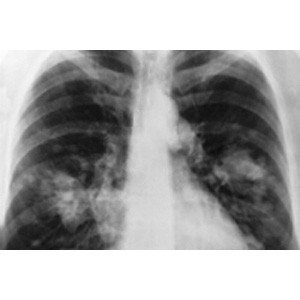

Results from a major phase III Cancer Research UK-funded trial show that elderly patients with advanced non small cell lung cancer (NSCLC) who developed a rash within 28 days of receiving the targeted drug erlotinib (Tarceva) survived on average 6.2 months, compared to 4.1 months for patients who were given a placebo. The study, led by Professor Siow Ming Lee (clinical researcher for Cancer Research UK at the UCL Cancer Institute), is published in the journal Lancet Oncology . For patients who, in addition to developing the painless rash, also carried mutations in the epidermal growth factor receptors (EGFR) on the surface of their cancer cells, the survival time was even greater at 10.4 months. Around eight in 10 cases of this form of lung cancer occur in people aged 60 and over, and the average age of patients in the UK is 72 years. Many of these elderly patients are diagnosed at a late stage and already have other illnesses, meaning they are often too frail to be treated with conventional chemotherapy. This means that palliative care is usually the only option available to them. These trial results show that giving erlotinib to these patients can significantly improve survival, if they develop a rash due to the drug.